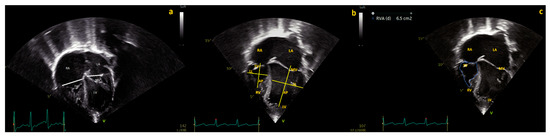

| Maskatia SA, 2018, USA [1] | 81 PA IVS Undergoing PBPV Age 3 (2–4) days | BVR, RV growth |

Baseline RV area ≥ 0.6 cm2/m2 (Sensitivity 93%, specificity 80%, AUC 0.88, odds ratio 50.4) Follow-up RV area ≥ 0.8 cm2/m2 sensitivity 100% specificity 100%, AUC 0.96, odds ratio 67) More than moderate TR |